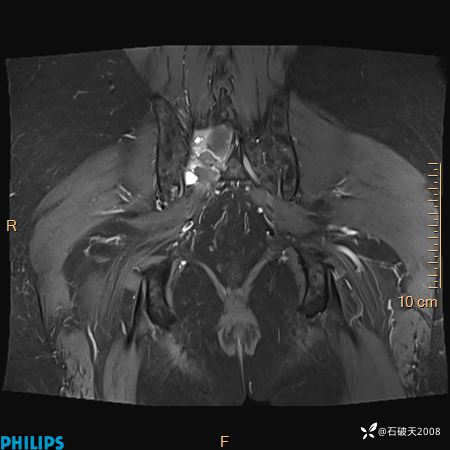

2023年3月份MRI影像

增强轴位